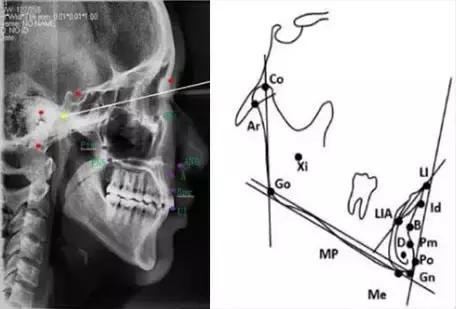

下颌标志点

髁顶点(Co.condylion):髁突的最上点。

关节点(Ar.articulare):颅底下缘与下颌髁突颈后缘之交点。关节点常在髁顶点不易确定时而代替髁顶点。

下颌角点(Go.gonion):下颌角的后下点。可通过下颌支平面和下颌平面交角之分角线与下颌角之相交点来确定

下齿槽座点(B.supramental):下齿槽突缘点与颏前点间之骨部最凹点。

下齿槽缘点(Id.infradentale):下齿槽突之最前上点。此点常在下中切牙之牙釉质-牙骨质界处。

下切牙点(Li.lower incisor):下中切牙切缘之最前点。

颏前点(P.pogonion):颏部之最突点。

颏下点(Me.menton):颏部之最下点。

颏顶点(Gn.gnathion):颏前点与颏下点之中点。

D点:下颌体骨性联合部之中心点。

这些标志点中,有些是在正中矢状面上,是单个的点。如鼻根点、蝶鞍点等。而有些则是双侧的点,如下颌角点,关节点等。若由于面部不对称而使两侧之点不重叠时,则取二点间的中点作为校正的位置。